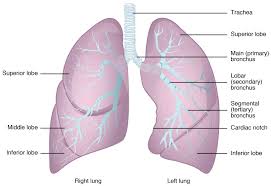

1. 폐암이란 무엇인가요?

폐암은 폐에 있는 세포가 비정상적으로 증식하는 질환으로, 크게 비소세포폐암과 소세포폐암으로 나뉩니다. 대부분은 비소세포폐암에 해당하며, 소세포폐암은 진행이 빠르고 전이가 잘 되는 특징이 있습니다.

폐는 산소와 이산화탄소를 교환하는 중요한 기관이므로, 암이 발생하면 호흡 기능에 치명적인 영향을 줍니다.